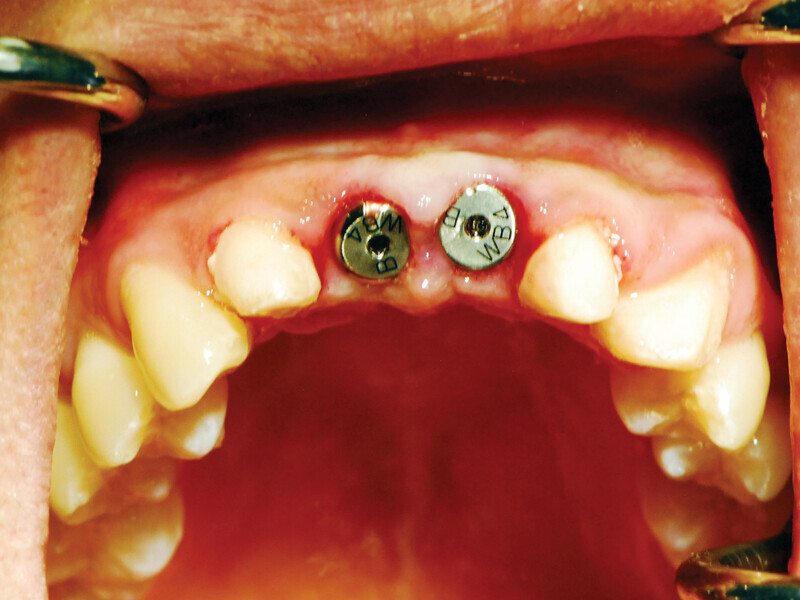

Figs. 4a: Implant to be uncovered (4a) presents with two options depending on width of attached gingiva available. Wide band of attached gingiva will remain after removal of tissue over cover screw, and the diode is utilized in a spiral pattern starting at center until fully exposed (4b). With the narrow band of attached gingiva present, an elliptical cut is made with the diode and tissue is pushed buccally and lingually to preserve the attached gingiva (4c). (Photo provided by Dr. Gregori M. Kurtzman)

Fig. 4b: Implant to be uncovered (4a) presents with two options depending on width of attached gingiva available. Wide band of attached gingiva will remain after removal of tissue over cover screw, and the diode is utilized in a spiral pattern starting at center until fully exposed (4b). With the narrow band of attached gingiva present, an elliptical cut is made with the diode and tissue is pushed buccally and lingually to preserve the attached gingiva (4c). (Photo provided by Dr. Gregori M. Kurtzman)

Fig. 4c: Implant to be uncovered (4a) presents with two options depending on width of attached gingiva available. Wide band of attached gingiva will remain after removal of tissue over cover screw, and the diode is utilized in a spiral pattern starting at center until fully exposed (4b). With the narrow band of attached gingiva present, an elliptical cut is made with the diode and tissue is pushed buccally and lingually to preserve the attached gingiva (4c). (Photo provided by Dr. Gregori M. Kurtzman)